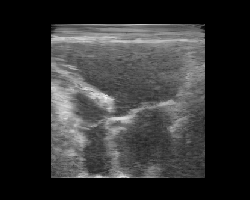

Latent Space Interpolation

Let’s pick two images, encode them, and interpolate between their latent representations. We’ll decode each interpolated latent and animate the result to visualize a smooth transition between two ultrasound images. Again, note that this model was trained on natural images only, and improved results are expected with a finetuned model on ultrasound data (to be added!).

Latent interpolation

You should see a smooth morphing between two ultrasound images, demonstrating the structure of the TAESD latent space.